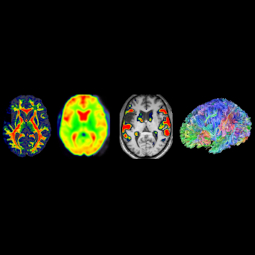

The ACN Lab is committed to conducting research that bridges cognitive neuropsychology and neuroscience with school psychology practice, to benefit children and adolescents in the schools. Our research is predominantly applied, ranging from the systemic level (policies in schools) to neuropsychological assessments. Research conducted within the ACN lab spans several topics within school psychology including learning disabilities, executive functioning, ADHD, traumatic brain injury, and working memory.